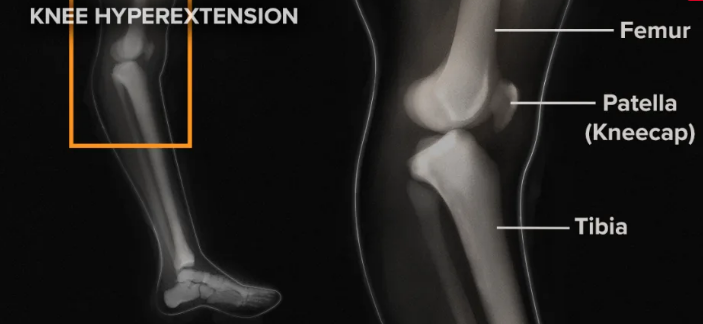

- 신체 검사: 외측 압력(varus stress test) 시 통증 및 관절 벌어짐 확인

- X-선 검사: 뼈 문제(비골 골절 등) 배제용.

- MRI: 인대 손상과 주위 조직 상태를 정확히 파악하는 데 가장 효과적